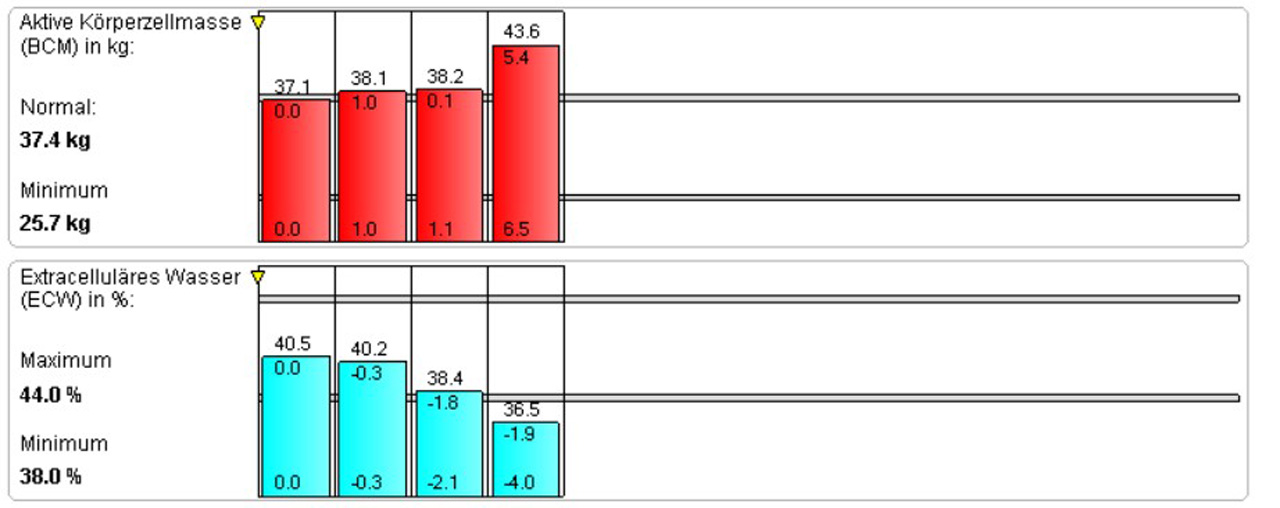

Darstellung der Auswertungs-Ergebnisse

Die Entwicklung und die Wirkungen der Trainingsmassnahmen und begleitender Ernährungsumstellungen können mittels Balkendiagramm dargestellt werden.

Dieser junge Patient macht seit Jahren Krafttraining. Man kann sehen, dass sich der Fettgehalt massiv reduziert hat, die BCM deutlich zugenommen hat und das ECW abgenommen hat.